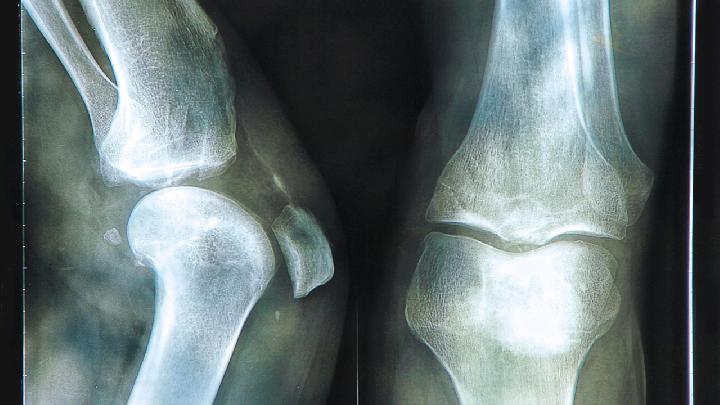

股骨粗隆间骨折的并发症主要是术后并发症。在治疗中,过去多行牵引保守治疗可使大多数患者骨折愈合,但长期卧床易引起肺部感染、褥疮、泌尿道感染和下肢静脉血栓形成,残疾率和死亡率高。

在手术中,使用内固定的患者经常并发拉力螺钉切割股骨头、髋内翻等并发症。